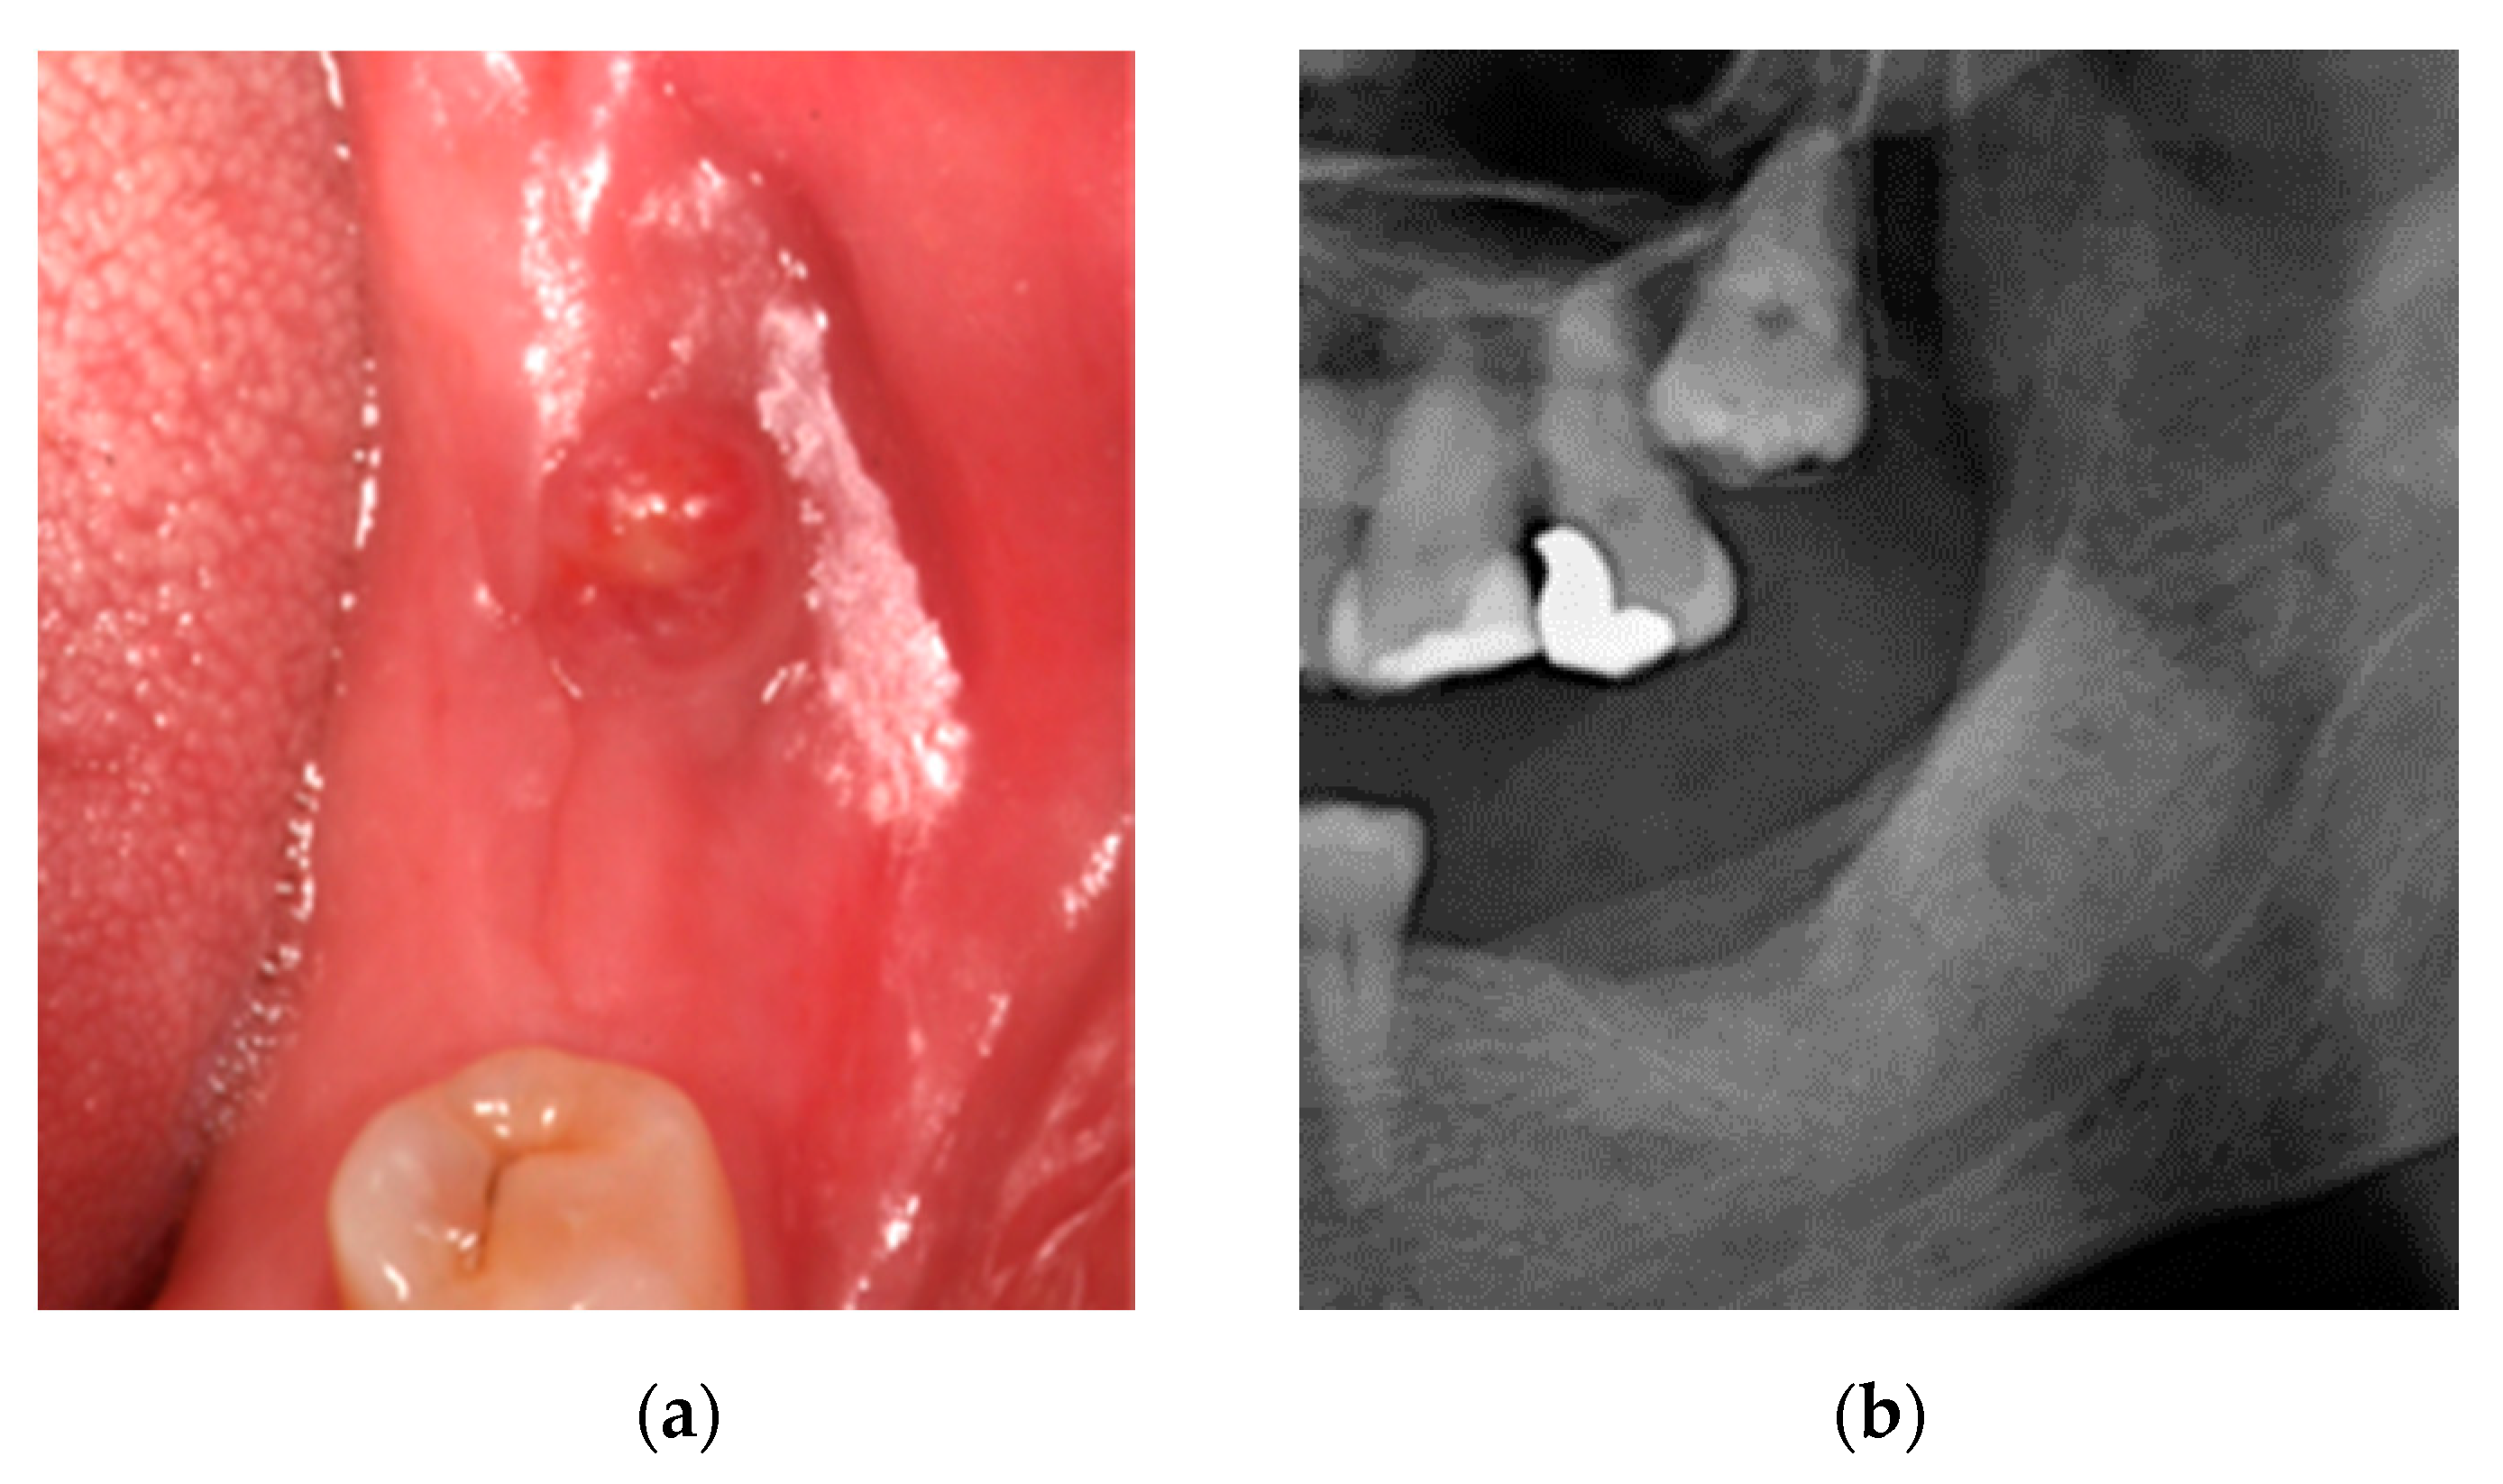

2.3. Case 3: Conservative Treatment + SURGERY + PRF-L

3. Results